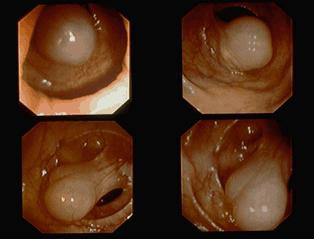

양성 비상피성종양 림프관종 (대장)

내시경적 용종절제술로 절제된 횡행결장의 림프관종

양성 비상피성종양/림프관종

대장/횡행

내시경

20~24